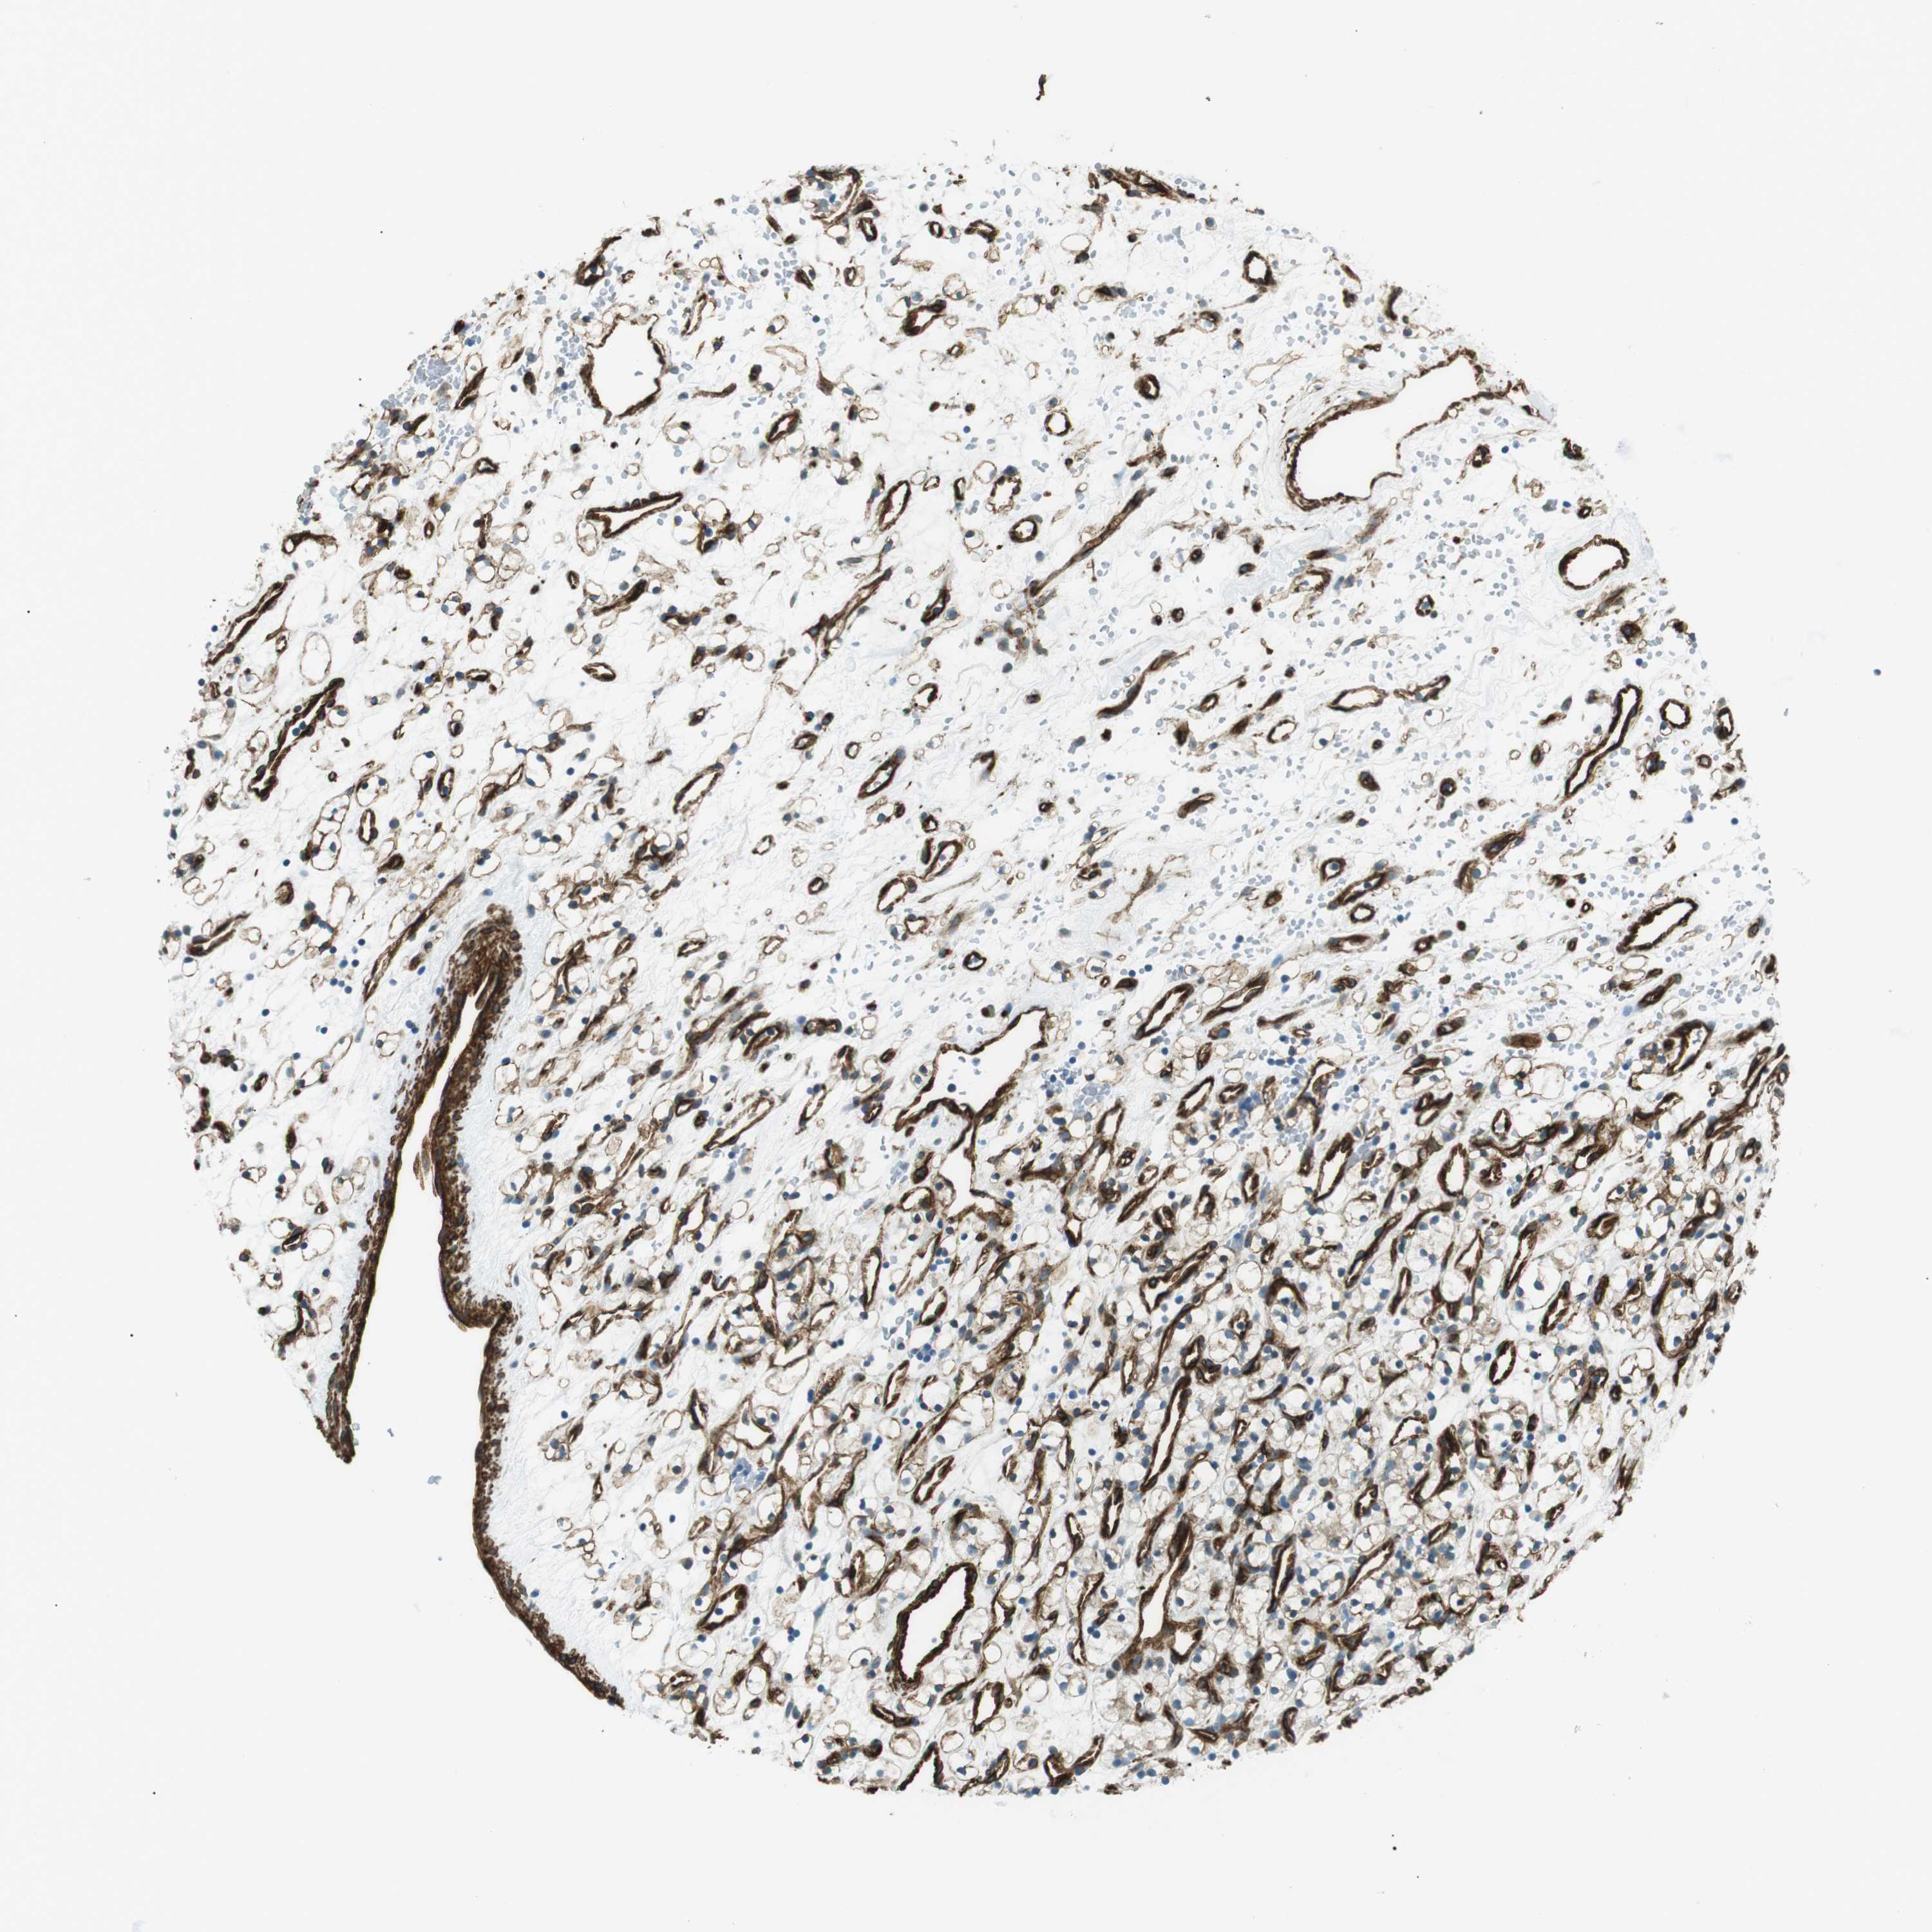

KIDNEY RENAL CLEAR CELL CARCINOMA (VALIDATION) - Interactive survival scatter ploti

The Survival Scatter plot shows the clinical status (i.e. dead or alive) for all individuals in the patient cohort, based on the same data that underlies the corresponding Kaplan-Meier plots. Patients that are alive at last time for follow-up are shown in blue and patients who have died during the study are shown in red.

The x-axis shows the expression levels (FPKM) of the investigated gene in the tumor tissue at the time of diagnosis. The y-axis shows the follow-up time after diagnosis (years). Both axes are complimented with kernel density curves demonstrating the data density over the axes. The top density plot shows the expression levels (FPKM) distribution among dead (red) and alive patients (blue). The right density plot shows the data density of the survived years of dead patients with high and low expression levels respectively, stratified using the cutoff indicated by the vertical dashed line through the Survival Scatter plot. This cutoff is automatically defined based on the FPKM cutoff that minimizes the p-score. The cutoff can be changed by dragging the vertical line or by entering a cutoff value in the square labeled "Current cut-off".

Under the Survival Scatter plot the p-score landscape (black curve; left axis) is shown together with dead median separation (red curve; right axis). Dead median separation is the difference in median mRNA expression between patients who have died with high and low expression, respectively. It is calculated as follows: median FPKM expression of dead patients with high expression - median FPKM expression of dead patients with low expression. This is intended to aid the user in visually exploring custom cutoffs and the associated p-scores and dead median separation.

Individual patient data is displayed and can be filtered by clicking on one or more of the category buttons on the top of the page. Categories describing expression level and patient information include: high, low, alive, dead, female, male and tumor stages. The scale of the x-axis can be toggled between linear and log-scale by clicking on the "x log" button. Mouse-over function shows TCGA ID, patient information and mRNA expression (FPKM) for each patient.

& Survival analysisi

Kaplan-Meier plots summarize results from analysis of correlation between mRNA expression level and patient survival. Patients were divided based on level of expression into one of the two groups "low" (under cut off) or "high" (over cut off). X-axis shows time for survival (years) and y-axis shows the probability of survival, where 1.0 corresponds to 100 percent.

ODR4 is not prognostic in Kidney Renal Clear Cell Carcinoma (validation)

Best expression cut offi

Based on the FPKM value of each gene, patients were classified into two groups and association between prognosis (survival) and gene expression (FPKM) was examined. The best expression cut-off refers the FPKM value that yields maximal difference with regard to survival between the two groups at the lowest log-rank P-value. Best expression cut-off was selected based on survival analysis .

When clicking on this number, the vertical dashed line indicating cut-off, the interactive survival plot, and the Kaplan-Meier curve will be adjusted to show results based on the best expression cut-off.

: 21.25

P scorei

Log-rank P value for Kaplan-Meier plot showing results from analysis of correlation between mRNA expression level and patient survival.

N/A

TCGA RNA samplesi

RNA-seq data is reported as average FPKM (number Fragments Per Kilobase of exon per Million reads), generated by the The Cancer Genome Atlas (TCGA) .

Normal distribution across the dataset is visualized with box plots, shown as median and 25th and 75th percentiles. Points are displayed as outliers if they are above or below 1.5 times the interquartile range. FPKM values of the individual samples are presented next to the box plot.

Average pTPM 20.2

Number of samples 100